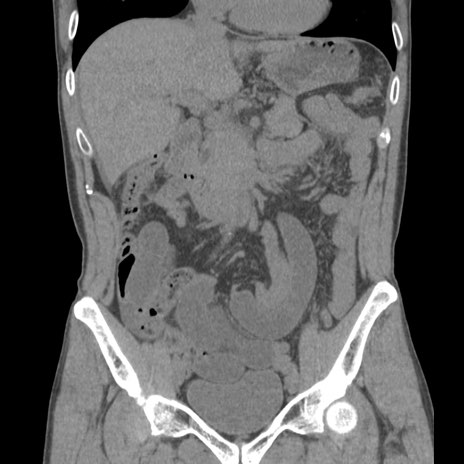

症例56 CT(冠状断像)

脂肪ウインドウ